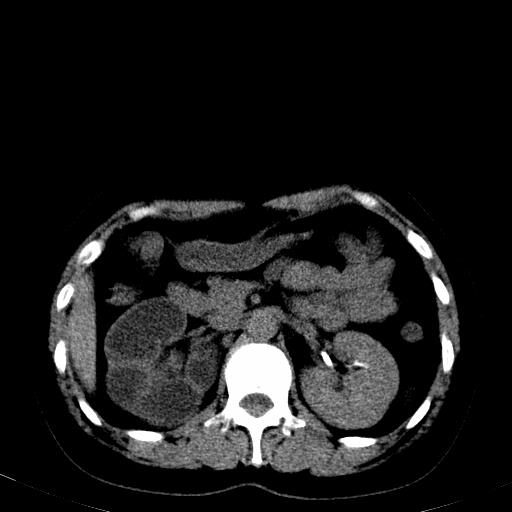

患者体检发现右肾体积增大,怀疑右肾积水

应该肾积水没有问题!

右肾多发囊肿,左肾、左输尿管结石

肾积水

右肾重度积水,以肾盏积水明显,有分隔,上段输尿管轻度扩张,管壁增厚,考虑肾结核可能,请结合尿检查,胸部拍片排除肺结核。

右侧肾积水、左侧肾结石

右侧肾积水、左侧肾结石  ,要排除右肾结核可能。

右肾重度积水,建议ct向下扫描或逆行造影,左肾及左输尿管结石 .

右侧肾积水、左侧肾结石 ,原因待查

患者尿常规正常,b超未发现明显结石,自身也无明显感觉异常。

请问多囊肾与肾积水怎么鉴别